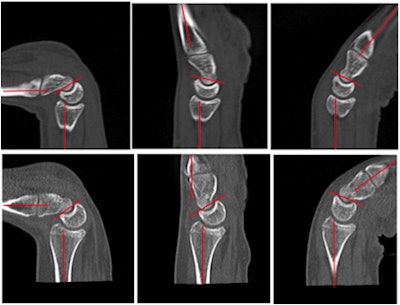

![]() ![]() Normal wrist motion in flexion and extension. Note that the lunate tracks the movement of the hand while remaining seated in the radius. All images and movies courtesy of Dr. John Troupis and Dr. Benjamin Amis.

![]() ![]() Abnormal wrist in motion. The lunate lags behind the movement of the hand until it snaps or clicks into line when just in flexion. The seating of the lunate in the radius is also affected.